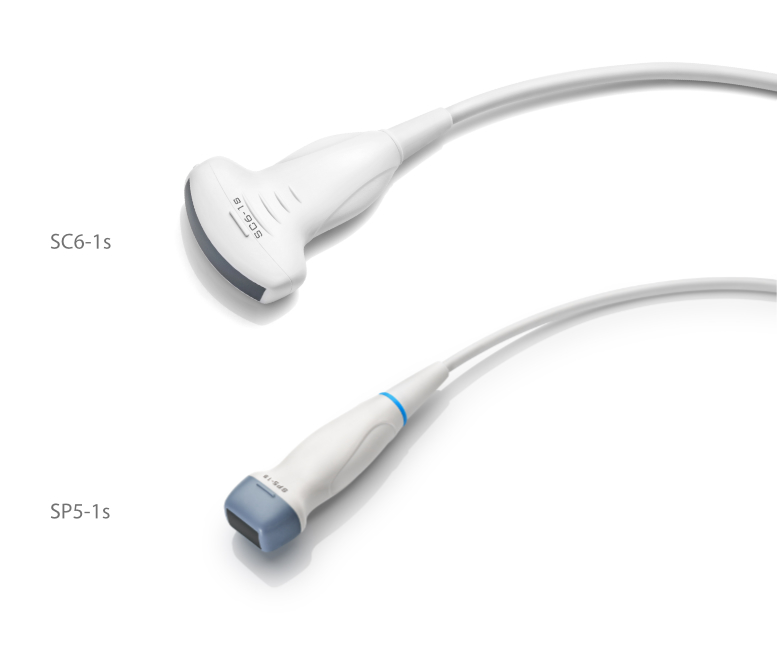

Transducers